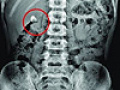

青少年体质连续25年下降 体检合格率低